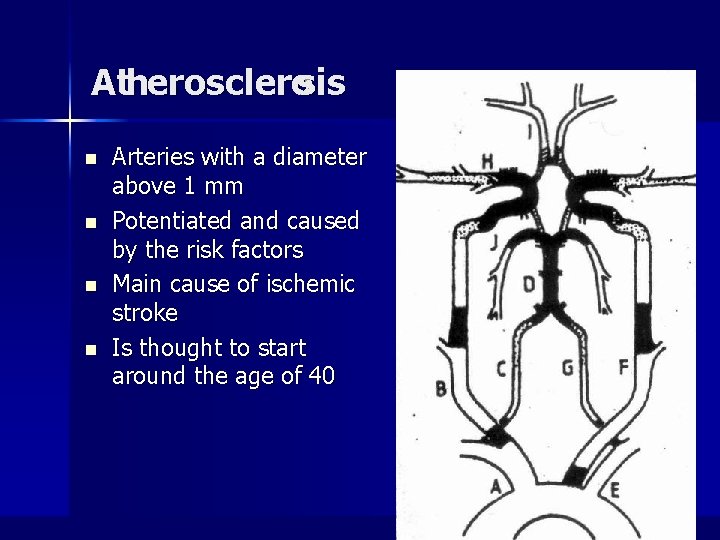

Atherosclerosis n n Arteries with a diameter above 1 mm Potentiated and caused by the risk factors Main cause of ischemic stroke Is thought to start around the age of 40